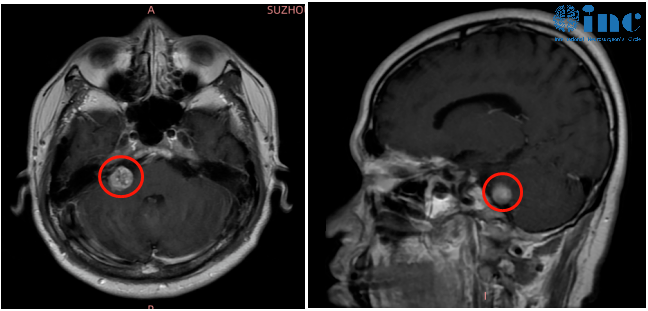

然而进一步的检查才让袁先生恐惧,右侧桥小脑角区结节,考虑听神经瘤。

肿瘤一大部分长在内听道深处,位置如此刁钻的肿瘤,手术难度可想而知。如果想要全切肿瘤不复发,手术需要磨除骨质极其容易伤及面听神经,更容易导致面瘫。